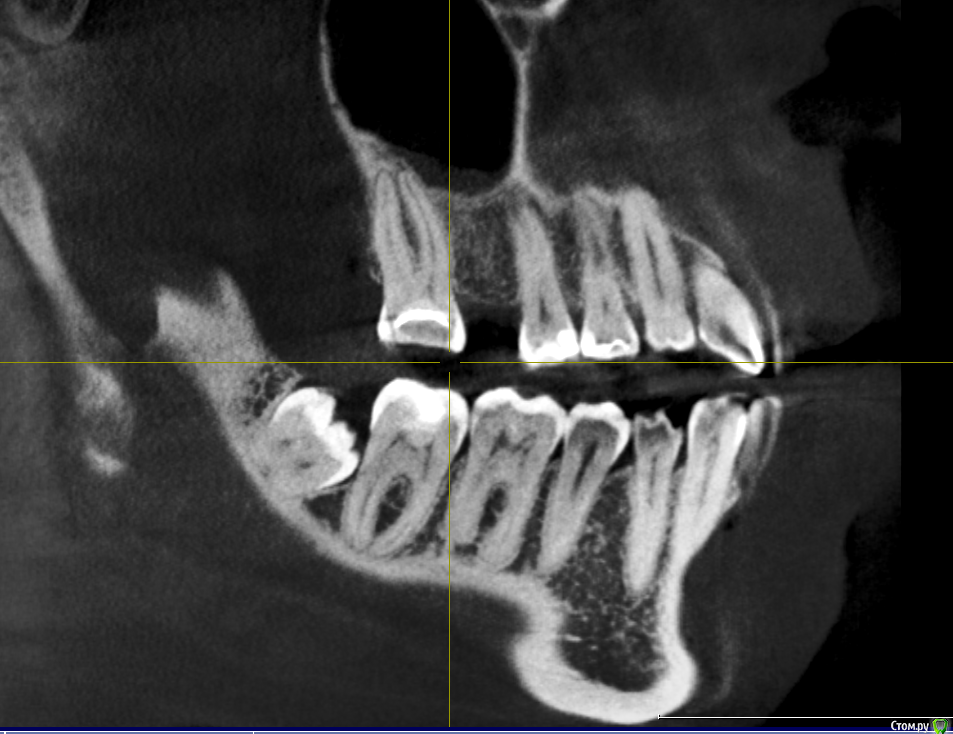

Mariia Опубликовано 9 ноября, 2017 Поделиться Опубликовано 9 ноября, 2017 Уважаемые доктора, добрый день!Посоветуйте, пожалуйста, что можно сделать в моем случае. Давно нет 3-х зубов (более 10 лет), стали стираться 7-ки справа, верхняя 6-ка слева стала опускаться.После нескольких консультаций окончательно запуталась в планах лечения.Понятно, что необходимо устанавливать 3 импланта, но как это сделать? - предлагают ортодонтическое лечение на верхней 6 справа (ставить миниипланты и поднимать) и верхней 7 слева (сдвигать ее, освобождая место для установки импланта, полностью имитирующий нормальный жевательный зуб). - и второе мнение: 7 не сдвигать, поставить вкладку, а 6 спиливать, депульпировать (скорее всего) и ставить керамическую вкладку. 6-ку не поднимать, так как гайморова пазуха находится близко к корню. Собственно, в комплексе с ортодонтией все лечение выходит очень дорогим.Что скажете? КТ по ссылкеhttps://yadi.sk/d/cSYIaF3p3PZFnb Ссылка на комментарий

Bier Опубликовано 10 ноября, 2017 Поделиться Опубликовано 10 ноября, 2017 Посмотрел Вашу КТ.Справа в принципе можно ортодонтией не заниматься, а поставить имплантат в позицию 16зуба, коронка будет чуть меньше стандартной. Проблемы скорее всего не будет. Слева ситуация сложнее. Надо удалить 28,38 зубы, внедрить на миниимплантатах 26з и имплантировать 36,37з Ссылка на комментарий

колесников Опубликовано 10 ноября, 2017 Поделиться Опубликовано 10 ноября, 2017 48,28,38 удалить. Импланты 16,36,37. Пластика десны в области имплантов 36,37. Керамическая вкладка (пломба) на 17,26,27 Ссылка на комментарий

Mariia Опубликовано 12 ноября, 2017 Автор Поделиться Опубликовано 12 ноября, 2017 Добрый день, и еще одно мнение: 7 справа не трогать, поставить вкладку. А в будущем провести ортодонтическое лечение: 7ку или поставить на место 6ки или отодвинуть и освободить место под полноценный имплант (доктор видит риск резорбции и травмы соседних зубов из-за недостатка места, тонкий имплант ставить не рекомендует)А слева предлагает сделать подсадку костной ткани на нижней челюсти - 6 и 7 зубы, чтобы поставить полноценный имплант (тонкий не рекомендует, хотя на прошлых консультациях мне предлагали как раз полноценный и костной ткани хватало). К сожалению, по моей КТ не показали, где идет истончение. Предложил сделать на другом оборудовании и с другим просмотрщиком, чтобы аргументировать свою точку зрения. Соответственно, 8 удаляем. Настолько ли моя КТ не информативна? Нужна ли КТ на операции? Возможен ли такой план лечения? Есть ли какой-то стандартизированный план лечения по моему случаю? Фото выложу чуть позже.Спасибо. Ссылка на комментарий